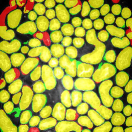

The first row in Figure 3 displays an original microscopy image (), its inhomogeneity corrected version (), and manually delineated groundtruth (), respectively. For brevity we have omitted the superscript in the notation. The second row shows segmentation results of various 3D methods such as 3D region-based active contours [10] (3Dac), 3D active contours with inhomogeneity correction [11] (3DacIC), and 3D Squassh presented in [12] (3Dsquassh). Similarly, the third row portrays various segmentation methods particularly designed for tubular structure segmentation such as ellipse fitting method presented in [15] (Ellipse Fitting), the Jelly filling method in [20] (Jelly Filling), and tubule segmentation using steerable filter [21] (Steerable Filter). Finally, the last row shows segmentation results of our proposed CNN architecture without inhomogeneity correction [27] (2DCNN) and with inhomogeneity correction (2DCNNIC).

For visual comparison we highlighted groundtruth regions in red, segmented tubule regions in green, and background in black. As observed in Figure 3, our proposed method appeared to perform better than the other six methods shown in the second and third rows by distinguishing tubules and was similar performance to 2DCNN. Note that since some methods such as Ellipse Fitting, Jelly Filling, and Steerable Filter only segmented boundaries of tubule structures, tubule interiors were filled in order to perform a fair comparison using connected components with a -neighborhood systems. Also, based on the assumption that tubule regions should contain lumen, if a filled region contained lumen pixel, the region was identified as a tubule region. However, if a filled region did not contain any lumen pixels, the region was considered as a background region.

The segmentation results shown in the second row generally missed many tubule regions. More specifically, 3Dac and 3Dsquassh could not capture the tubular structures but captured some in the center regions due to the intensity inhomogeneity of microscopy images. 3DacIC failed to segment tubular structures but captured multiple lumens inside tubules as well as some tubule boundaries. In contrast, the segmentation results displayed in the third row showed falsely detected tubules. The main reason is that these tubule segmentation methods focused only on detecting boundaries of tubular structures. In particular, due to weak/blurry edges of fluorescence microscopy images, many boundaries were not continuous causing the filling operation to overflow from one tubule to another or to the background regions. The segmentation results using the CNN generally successfully segmented and identified each tubule region.

Figure 4 provides an alternative way to show the segmentation results. In particular, yellow regions correspond to true positives which are pixel locations that are identified as tubules in both the groundtruth and segmentation results. Green regions correspond to false positives which are pixel locations that are identified as background in groundtruth but tubules in segmentation results. Similarly, red pixels correspond to false negatives, namely pixel locations identified as tubules in the groundtruth but background in segmentation results, and black pixel regions correspond to true negative that are identified as background in both groundtruth and segmentation results. The green regions indicate Type-I error (false alarm) regions and the red regions represent Type-II error (miss) regions. As observed from Figure 4, the segmentation results in the first row contained large red regions which mean large regions of tubules were missed. Conversely, the segmentation results shown in the second row contained many green regions indicating many background regions were falsely segmented as tubule regions. In contrast, the segmentation results in the third row had reasonably small green regions and red regions which indicate that the deep learning based segmentation results had higher pixel accuracy with relatively low Type-I and Type-II errors.